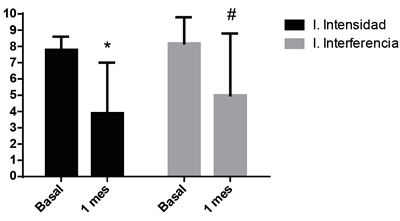

En esa población de pacientes respondedores, se observa que todos esos aspectos disminuyeron marcadamente. El EVN pasó de 8,8 ± 2,1 a 4,0 ± 3,1 con un porcentaje de cambio de 54 % (p < 0,0001), el índice de intensidad de 7,8 ± 0,8 a 3,9 ± 3,1 (50 % de porcentaje de cambio, p = 0,0001) el índice de interferencia, de 8,2 ± 1,6 a 5,0 ± 3,8 (40 % de cambio, p = 0,0027) y el catastrofismo total de 37 ± 13 a 17,5 ± 16 (57 % de cambio, p < 0,0001) (Figuras 5 y 6).

Fig. 5. Índices de intensidad y de interferencia basales y al mes de la inyección epidural de esteroides, en el grupo de pacientes definidos como respondedores (n = 16) (p < 0,05, test de t para muestras dependientes).